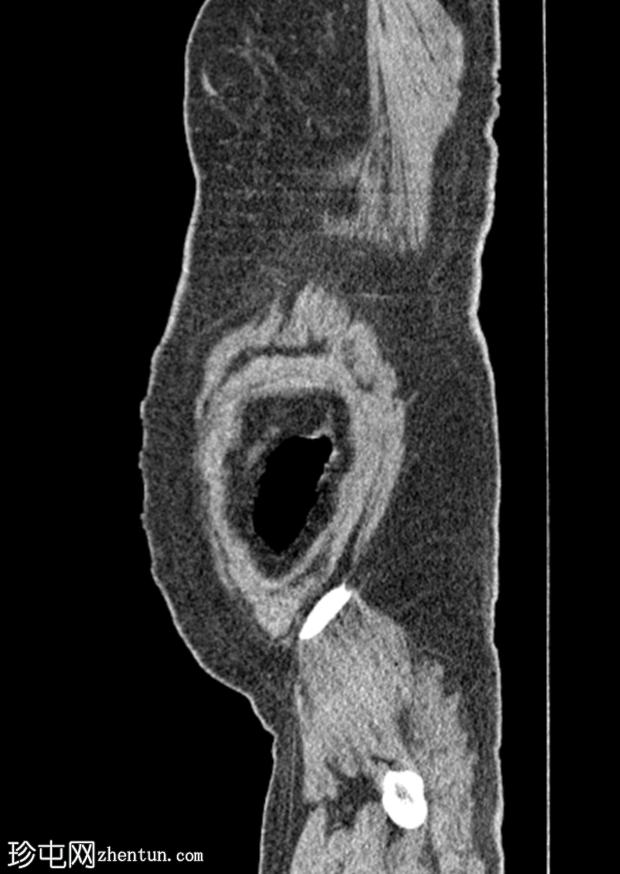

矢状位

非增强扫描

可见阑尾后方炎症,阑尾尖端积液,肾后间隙可见大量气体,炎症延伸至肝周、腰大肌后方及腹壁筋膜平面,符合阑尾穿孔引起的广泛性坏死性筋膜炎的

影像

学表现。